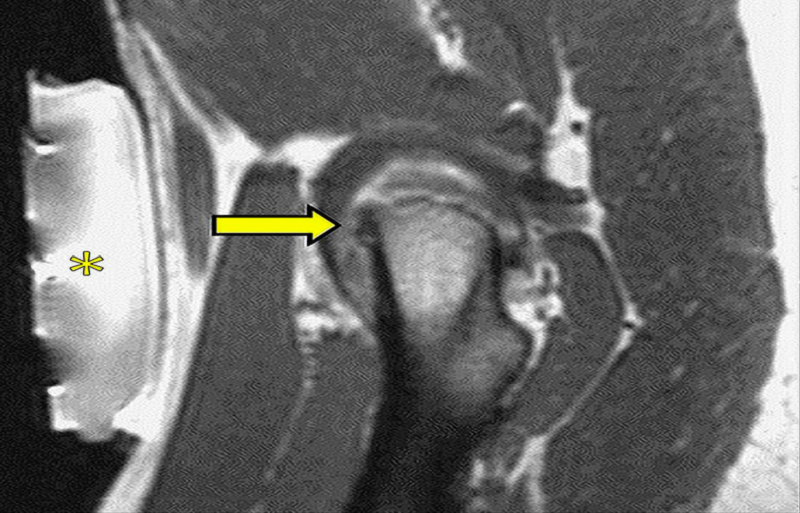

圖:磁共振引導下的復發(fā)性軟組織腫瘤冷凍消融

另一個優(yōu)點是可以連續(xù)(即使是雙傾角,典型的超聲制導),加上熱控制,評估燒蝕區(qū)域。

消融的圖像引導通常由MRI表示,為正確的光束瞄準和溫度映射提供解剖信息。

已經開發(fā)了針對內臟器官和軟組織損傷的多種應用。腎臟代表適合活檢和消融的目標。MRI非常適合前列腺病變的檢測和分期??梢越Y合超聲和MRI進行前列腺活檢或直接進行孔內活檢,利用實時MRI的優(yōu)勢來確認針位,消除配準錯誤或影響融合成像的器官運動,并使用經會陰而不是經直腸途徑降低細菌感染風險。已經描述了多個在安全性和并發(fā)癥方面具有良好結果的消融病例;即使局部和全腺體消融都安全有效地進行,主要問題仍然是適應癥。根據描述肝臟消融的經驗,MRI引導是可能的,但超聲的方法似乎更可行。